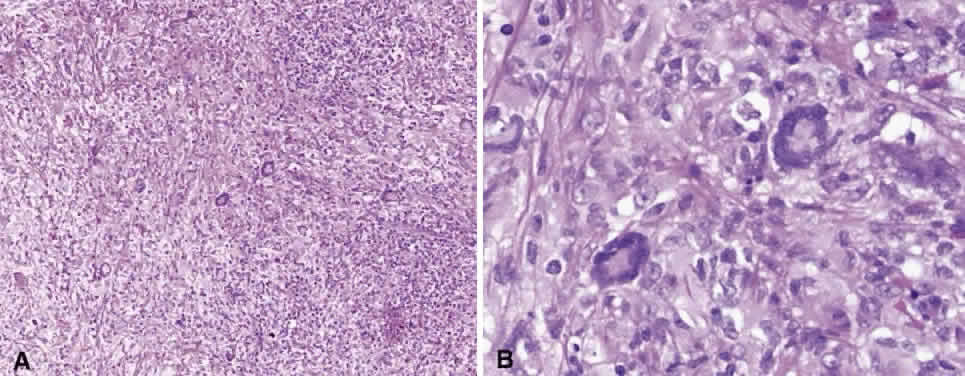

Numerous attempts have been made to classify lymphoid processes for clinical management and prediction of prognosis. Early classifications included only disease localized to the lymph node, which made classification of extranodal disease difficult and inaccurate. The Rappaport classification, first developed in 1956 and then modified in 1978, attempted to categorize lymphomas in two ways, first, using cytologic characteristics identified by conventional stains, and second, distinguishing between the follicular and diffuse growth pattern histologically38,39 (Table 3). The distinction of nodular, or follicular, and diffuse growth was considered useful because of the generally indolent nature of follicular growth, in which the tumor cell aggregates resemble germinal centers and disrupt the normal architecture of the node, compared with the appearance of diffuse growth, in which the lymph node is completely obliterated by a dense monotonous sheet of lymphocytes. In subsequent years, however, it was found that the descriptive growth pattern and cytogenetic characteristics of the Rappaport system did not predict prognosis reliably and were biologically inaccurate. The complexity of correlating degrees of differentiation, mitotic activity, and cytologic characteristics to prognosis have made lymphomas difficult to classify and have led to subsequent systems. The second system, proposed by Lukes-Collins in 1974, classifies lymphoma histologically according to its normal counterpart B-cell, T-cell, or null cell origin40,41 (see Table 3). Histologically, cells may appear small cleaved, large cleaved, small noncleaved, or large noncleaved, depending on the stage of B-cell arrest during normal transformation to immunoblast. Ninety percent of lymphomas are of B-cell origin, and the null cell also usually is of B-cell origin, although 10% may originate from T cells or histiocytes.42,43 Burkitt's lymphoma, the only lymphoma common in children, is a B-cell variant with a background of reactive histiocytes. As a result of histologic classification by Lukes-Collins, 76% of histiocytic lymphomas according to the Rappaport system were found to be not of histiocytic origin but of lymphocytic origin.40,44 The third system, the Working Formulation devised by the National Cancer Institute in 1982, attempted to predict prognosis by grouping lymphoma according to natural history, response to therapy, and overall survival.45 Three broad categories were established in terms of 5-year survival rates, the low-grade with a 50% to 70% survival rate, intermediate with 35% to 45%, and high grade with 23% to 32% (see Table 3). Orbital reactive hyperplasia, a relatively low-grade lesion, can be associated with systemic disease, whereas malignant or high-grade orbital lymphomas may be isolated findings. The Ann Arbor Staging Classification for Hodgkin's and non-Hodgkin's lymphomas was developed to stage disease based on systemic areas of involvement as a means of establishing a baseline for treating disease and following clinical progression46 (Table 4). Histologic classification, however, has been recognized as more useful than localization in the clinical management of nonHodgkin's lymphoma.47